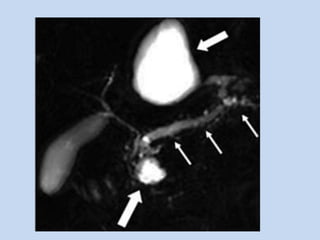

• In Cholangiocarcinoma :

- MRCP is very accurate in identifying the presence &

level of neoplastic obstruction of pancreatobiliary

tract.

- In conjunction with conventional MR + MRCP and ,

when necessary MRA permits not only diagnosis but

also staging of malignant tumors of pancreatobiliary

• In hilar cholangiocarcinoma, it depicts the length of

extra-hepatic bile duct involved by the disease as well

as the proximal extent of the disease – an important

factor in determining the resectability.